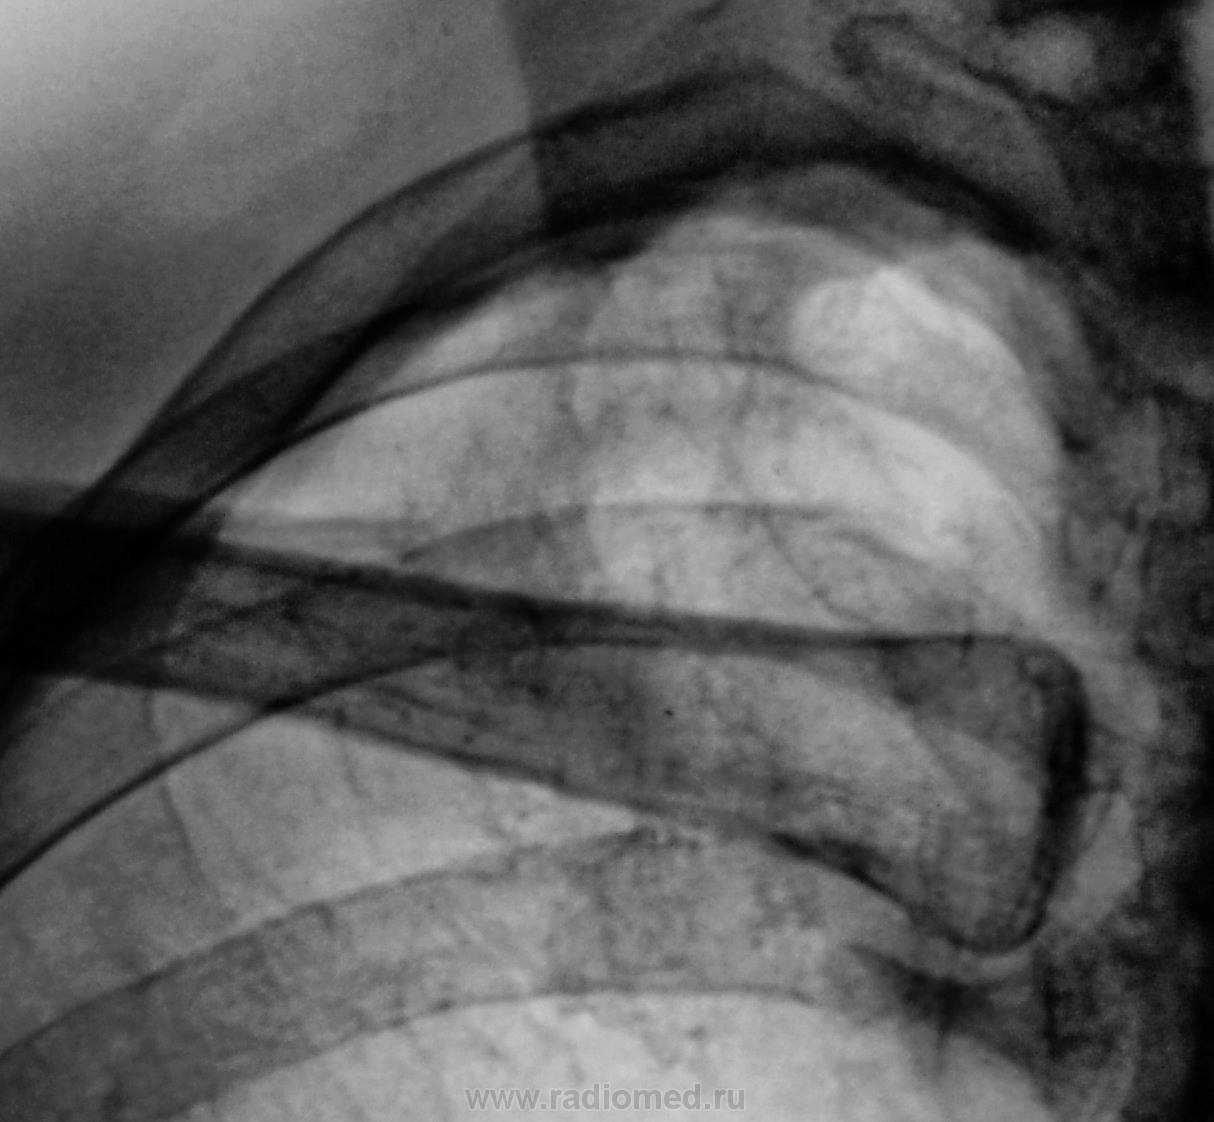

Взяли на контроль, смутили очаги на верхушке.

Томограммы.

.... и меня тоже))))...причем и левая тоже))))- очаговая тень на фоне 1-го ребра и немного за него выступающая....